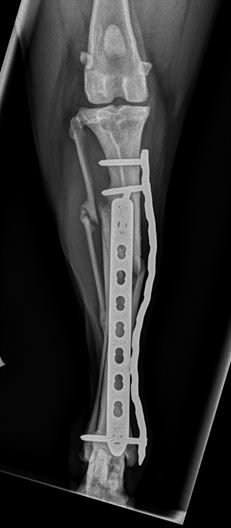

After assessing the CT images it was decided that standard plating procedures would carry a significant risk of the fissure propagating, but that a double plating technique using a single locking screw at the lower end of each plate would minimise this risk whilst achieve the minimum requirement for stable fixation. Locking screws have threaded heads that ‘lock’ into the plate. The CT showed that a fissure extended to within 10 mm of the joint surface, but confirmed that it would be safe to place two locking screws at 90 degrees to each other and avoid the fissure and the joint surface.

Two locking compression plates (LCP’s) were applied to the right tibia, one on the cranial aspect of the bone, and one on the medial aspect of the bone. Post operative radiographs showed that the tibia was suitably aligned and that the most distal screw had successfully avoided the joint surface and the fissure.

Indie was cage rested for 6 weeks, with regular short toilet walks outside. Follow up radiographs were taken after 6 weeks which showed good progression of bone healing. Exercise was cautiously increased and at at the final recheck 11 weeks after surgery the owner was not seeing any signs of lameness and was able to build up to normal exercise.